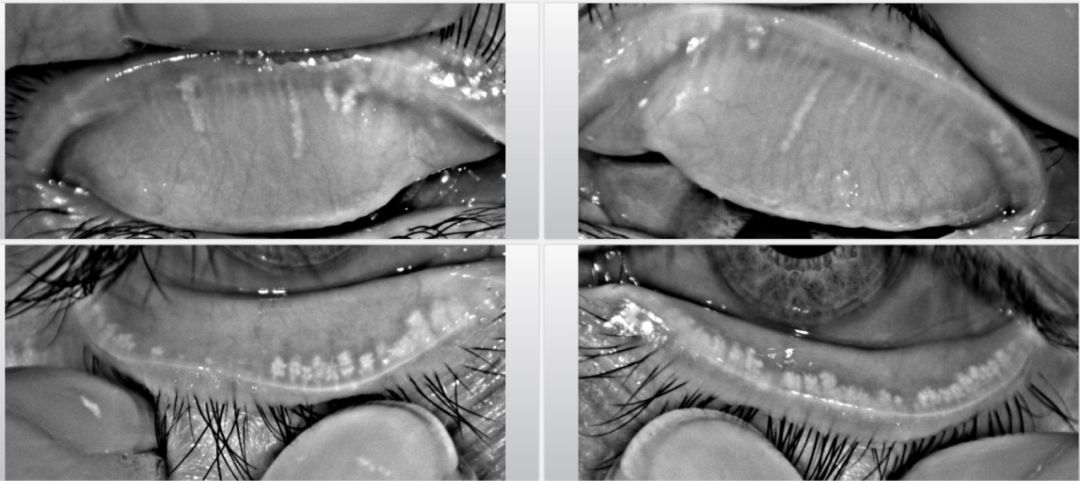

(1)眼部因素:前部睑緣炎、佩戴角膜接觸鏡、蠕形螨感染以及幹眼等眼表長期慢(màn)性炎性反應。

通常睑闆腺功能障礙患者睑闆腺分泌的油脂質量不好,不易排出,造成睑闆腺堵塞。長期的堵塞,睑闆腺就不再分泌油脂,就會造成睑闆腺萎縮。睑闆腺堵塞或萎縮都就會導緻淚膜油脂缺乏,從而出現(xiàn)眼幹澀、眼痛、眼磨、燒灼感、異物感、時常伴有視力模糊、視力波動,眼部分泌物增多等情況。所以,睑闆腺功能障礙需要綜合性治療,包括用藥、睑緣清潔、除螨濕巾、濕房鏡、睑闆腺按摩(SPA)和“光潤”強脈沖(OPT)等,且大多需要進行周期性治療。